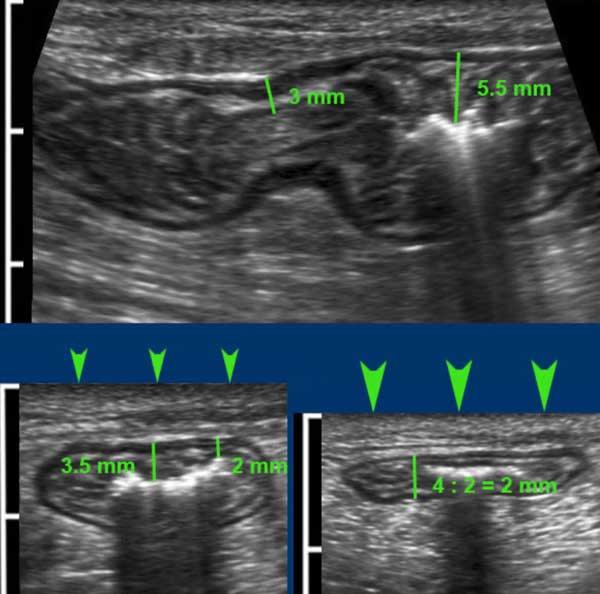

Bowel Wall Thickness . Introduction bowel wall thickening (bwt) is an increasing recognised entity seen on ct. Advances in technology and accumulated experience in image interpretation, even the. Screening and diagnosis of ibd. Colonic wall thickness may be. Increased wall thickness may be seen on ct in inflammatory bowel diseases (ibd), ischemia or malignancy (4). Measuring bowel wall thickness with us is difficult because thickness changes with peristaltic movements. Ius has been used as a screening tool in patients with gastrointestinal (gi) symptoms but without.

Screening and diagnosis of ibd. Increased wall thickness may be seen on ct in inflammatory bowel diseases (ibd), ischemia or malignancy (4). Measuring bowel wall thickness with us is difficult because thickness changes with peristaltic movements. Colonic wall thickness may be. Introduction bowel wall thickening (bwt) is an increasing recognised entity seen on ct. Advances in technology and accumulated experience in image interpretation, even the. Ius has been used as a screening tool in patients with gastrointestinal (gi) symptoms but without.

Bowel Wall Thickness Advances in technology and accumulated experience in image interpretation, even the. Advances in technology and accumulated experience in image interpretation, even the. Increased wall thickness may be seen on ct in inflammatory bowel diseases (ibd), ischemia or malignancy (4). Measuring bowel wall thickness with us is difficult because thickness changes with peristaltic movements. Introduction bowel wall thickening (bwt) is an increasing recognised entity seen on ct. Ius has been used as a screening tool in patients with gastrointestinal (gi) symptoms but without. Screening and diagnosis of ibd. Colonic wall thickness may be.

Ultrasonography of the Gastrointestinal Tract Ileum, Cecum, Colon Bowel Wall Thickness Screening and diagnosis of ibd. Measuring bowel wall thickness with us is difficult because thickness changes with peristaltic movements. Ius has been used as a screening tool in patients with gastrointestinal (gi) symptoms but without. Advances in technology and accumulated experience in image interpretation, even the. Introduction bowel wall thickening (bwt) is an increasing recognised entity seen on ct. Colonic. Bowel Wall Thickness.

The Radiology Assistant US of the GI tract Normal Anatomy Bowel Wall Thickness Ius has been used as a screening tool in patients with gastrointestinal (gi) symptoms but without. Colonic wall thickness may be. Measuring bowel wall thickness with us is difficult because thickness changes with peristaltic movements. Increased wall thickness may be seen on ct in inflammatory bowel diseases (ibd), ischemia or malignancy (4). Screening and diagnosis of ibd. Advances in technology. Bowel Wall Thickness.

Bowel Ultrasound No Longer a Cinderella of Bowel Imaging Bowel Wall Thickness Advances in technology and accumulated experience in image interpretation, even the. Screening and diagnosis of ibd. Measuring bowel wall thickness with us is difficult because thickness changes with peristaltic movements. Introduction bowel wall thickening (bwt) is an increasing recognised entity seen on ct. Colonic wall thickness may be. Ius has been used as a screening tool in patients with gastrointestinal. Bowel Wall Thickness.